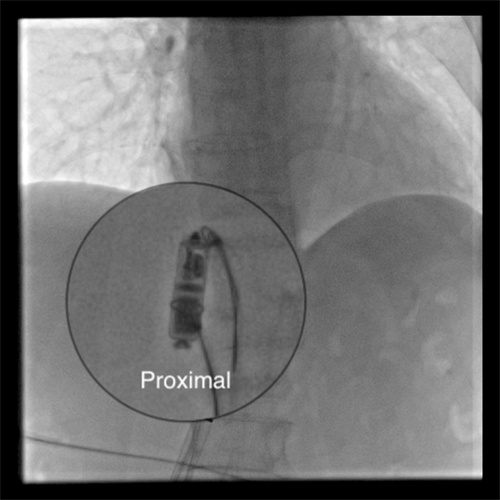

采用单通道双圈套器技术成功捕获到起搏器

近日,捷克论坛 集团澧县人民医院利用介入技术成功处理了一位八旬老太的罕见“心”事。这位八旬老太因反复出现心慌来到医院。经检查发现是植入的无导线起搏器出现移位,并发频繁地异位起搏,并且脱落的起搏器在心脏里到处乱串,严重威胁到老人生命安全。捷克论坛 派驻澧县人民医院的颜鹏副院长接手后,率领当地介入血管外科和心内科紧急制定处理方案。在没有可借鉴经验的困难情况下 ,创新性地采用单通道双圈套器技术,仅仅通过腿部米粒大小的穿刺针道,成功取出了这个脱落的起搏器,该患者也得到了顺利救治康复出院。查阅相关文献,这也属于国际上罕见的成功处置案例。

颜鹏副院长介绍,近年来,随着高新技术新材料的涌现,新的治疗手段也在不断更新。此次取出的无导线起搏器起搏器就是2019年才进入国内的一种新的植入型起搏器。但由于老年患者的心脏结构出现退化,起搏器植入后锚定不理想,在特定情况下就会出现脱落移位。脱落的起搏器不仅不能起到治疗效果,还会因为起搏器的异位刺激,导致频繁的心率失常。另一方面,脱落的起搏器会在心脏内乱串,甚至会堵塞血流通道,导致患者猝死。此次在缺乏可供参考的经验情况下,捷克论坛 与澧县人民医院的介入团队通力协作,成功处置了这起罕见的心脏异物事件。不仅体现了介入技术的神奇之处,也是近年来捷克论坛 通过医联体下沉优势技术成果的一次考验,也为国内以后处理此类事件积累到了很重要的经验。切实体现了人民医院为人民,仁心仁术为人民的“仁术”精神。(澧县人民医院介入血管外科 童方 捷克论坛 介入血管外三科 颜鹏)